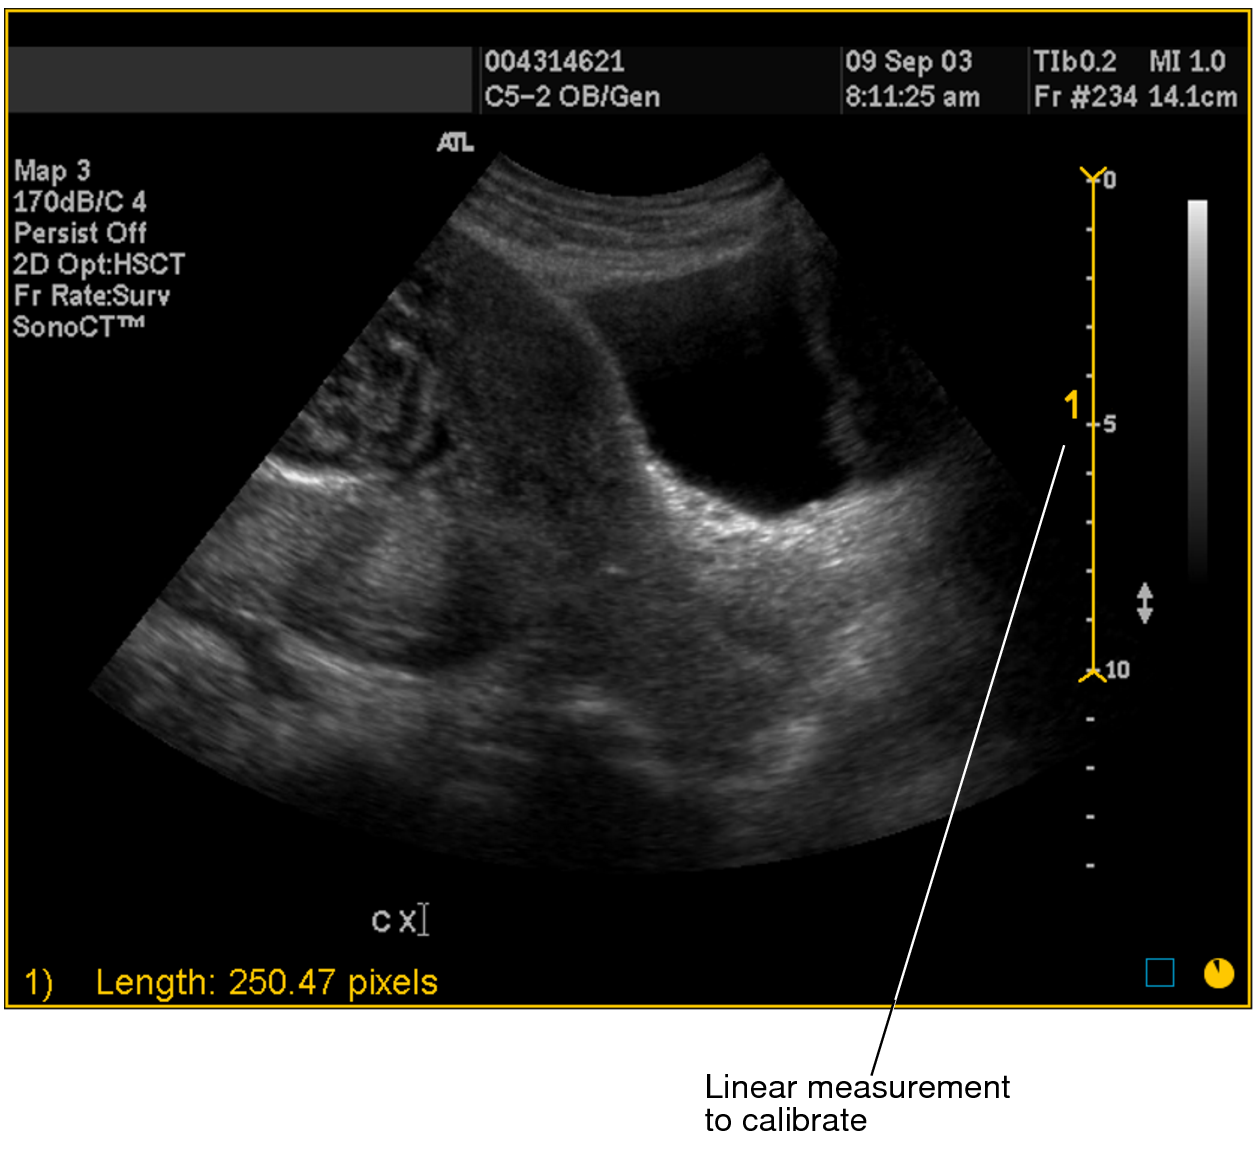

3. Click at the starting point of your measurement and drag. Release the mouse button at the end of your measurement.

A numbered measurement line appears, and the corresponding length appears in the bottom left corner of the viewport. Notice that the length is displayed in pixels.

Linear measurement to calibrate